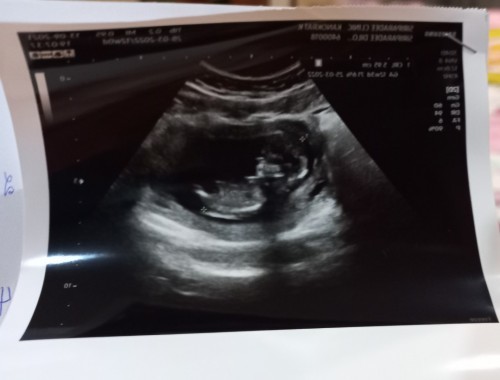

อยากเห็นภาพอัลตร้าซาวด์ของแม่ๆคะเอามาอวดกันหน่อยคะ กี่weekกันแล้วบ้างเอ่ย ส่วนตัวแม่12weekแล้วคะ

12w6d ค่ะ ประมาณ 6cm. ตอนแรกจะไม่ได้ซาวด์หน้าท้อง แค่ฟังเสียงหัวใจเฉยๆ แต่น้องไม่ยอมให้ฟัง เลยต้องซาวด์ค่ะ ตกใจทั้งแม่ทั้งหมอเลย สรุปน้องสมบูรณ์ดีค่ะ ยังไม่ทราบเพศจ้า

น้อง12weekแล้วค่ะ ยกแขนยกขาโชว์เลยตื่นเต้นและดีใจมากๆเลยค่ะรอลุ้นว่าเดือนหน้าน้องจะให้เห็นเพศไหม😊😊 #ทีมท้องแรกค่ะ